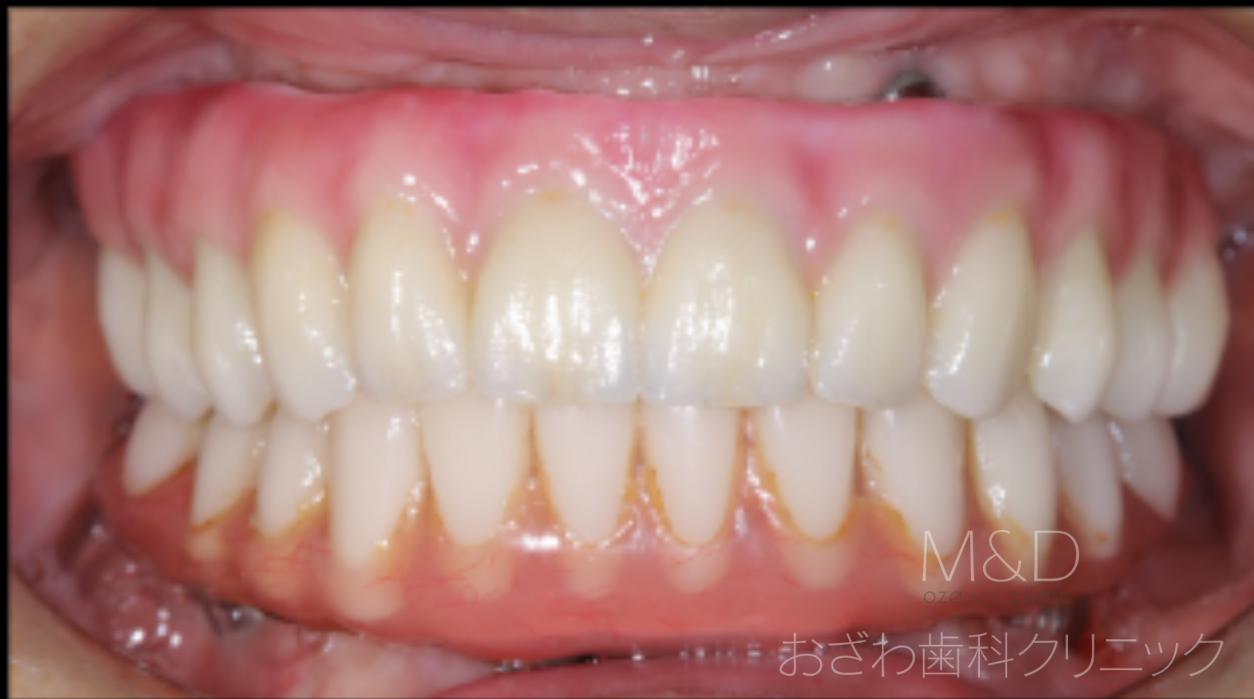

術後

上顎 340万円(税別)フルジルコニアオールセラミック

下顎 250万円(税別)アクリル